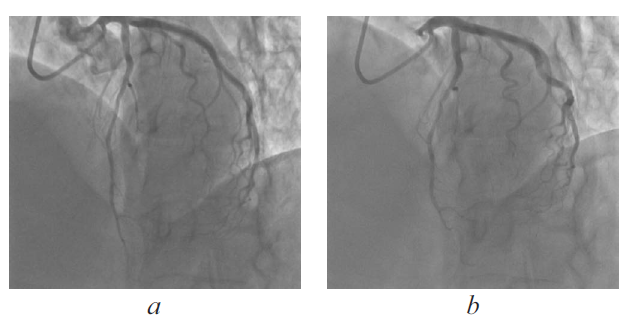

Cardiovascular diseases (CVDs) are the leading cause of mortality among the population. At the core of the progression of the coronary heart disease is the atherosclerosis of the coronary arteries, which is found in majority of patients suffering from angina and in patients with myocardial infarction. However, in some cases, coronary angiography reveals, that patients with the mentioned clinical manifestations have their coronary arteries unchanged. This is treated as syndrome X or microvascular angina. Along with that, development or aggravation of the coronary heart disease may be based on the congenital peculiarities in the coronary arteries location and structure, such as muscular bridges and fistulas of the coronary artery. This is confirmed by a number of studies, which indicate the role of the above mentioned pathologies in the occurrence of angina and myocardial infarction. Nevertheless, there is also the opposite view, which is supported by a number of specialists. According to them, the presence of the mentioned peculiarities in the structure of the coronary channel is deemed as the patient-specific norm. Hence, the issue of the surgical treatment of the patients with the aforementioned coronary arteries anomalies remains controversial. The clinical case report of the patient with the symptoms of angina pectoris, in which the coronary angiography did not reveal the stenosis of the coronaries arteries, but located the myocardial bridge and the coronary fistula. The role of the congenital coronary vessels pathology in the angina pectoris is analyzed. The diagnosis guidelines and the tactics of the conservative and surgical treatment of patients with the above mentioned syndromes are discussed.